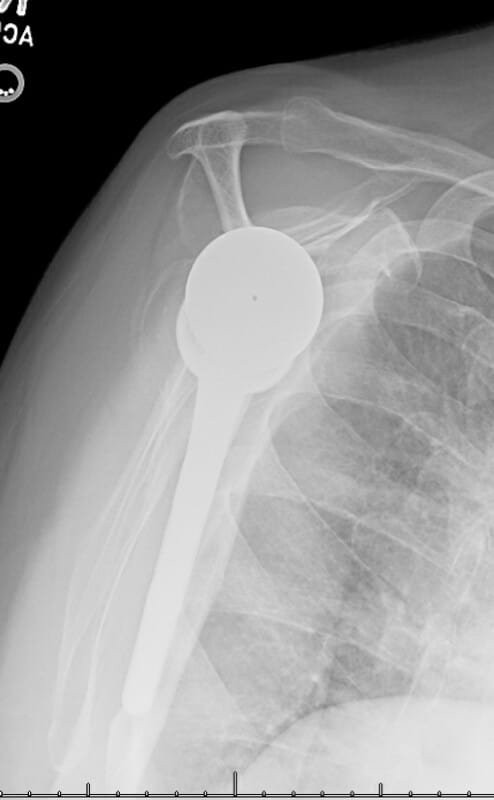

DePuy, DeltaXtend